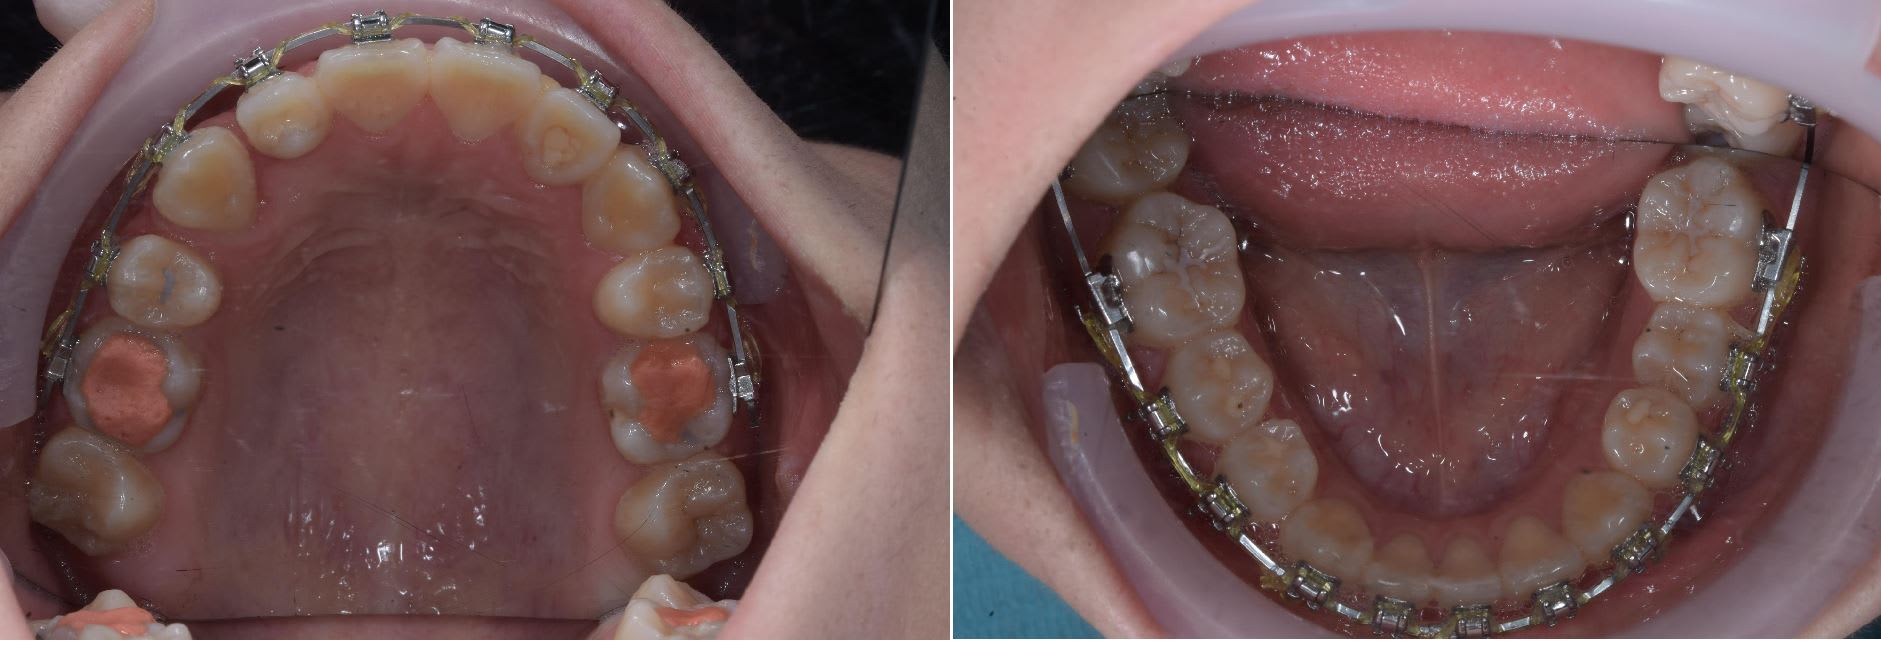

Patiente ayant commencé son traitement en Nouvelle Zélande, le dentiste lui ayant dit qu'elle en avait pour un ou deux mois grand max pour finir.

Discussion un peut tendue avec la maman pour expliqué que non en un mois ça allait pas être possible, qu'il fallait plutôt un ans et extraire une incisive du bas ( car en cas d'agénésie la substitution c'est un peut la meilleur solution )

Enfin bref, prise d'empreinte pour un set up 3D et extraction 2 semaines plus tard.

La patiente à était une championne avec les élastique et 5 mois plus tard ( ou aujourd'hui ) ont à put enlever les bagues.

C'est pas parfait mais c'est mieux que de continuer en Suisse ( car la maman à déjà payé pour le traitement en NZ, au Cambodge et trouve qu'il n'y a pas matiére à continuer les dépenses en Europe ).

On va lui donner demains des aligneurs plastique pour améliorer l''alignement et le traitement sera fini à son retour dans deux ans.

L'extraction d'une incisive inf pour traiter un cas d'agénésie inf c'est pourtant pas très courant comme modalité de traitement.

Au maxillaire , il manque deux premolaires.

Est-ce une agenesie des "5" maxillaires ?

Ou bien des extractions pour corriger la malocclusion ?

la substitution est une bonne alternative afin de terminer en classe 1 canine et molaire droite et gauche et assurer par conséquence la stabilité à long terme .

on dirait que la 33 a pris la place de la 32 !

la 23.24.33 doivent être tipper et c' est bon .